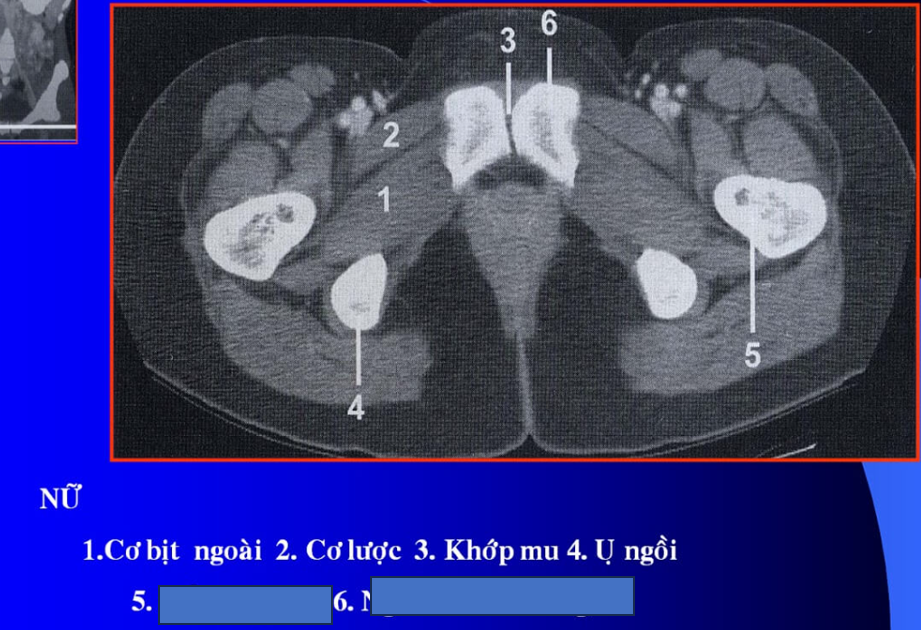

cq trong hình ?

cơ tl? cơ chậu?